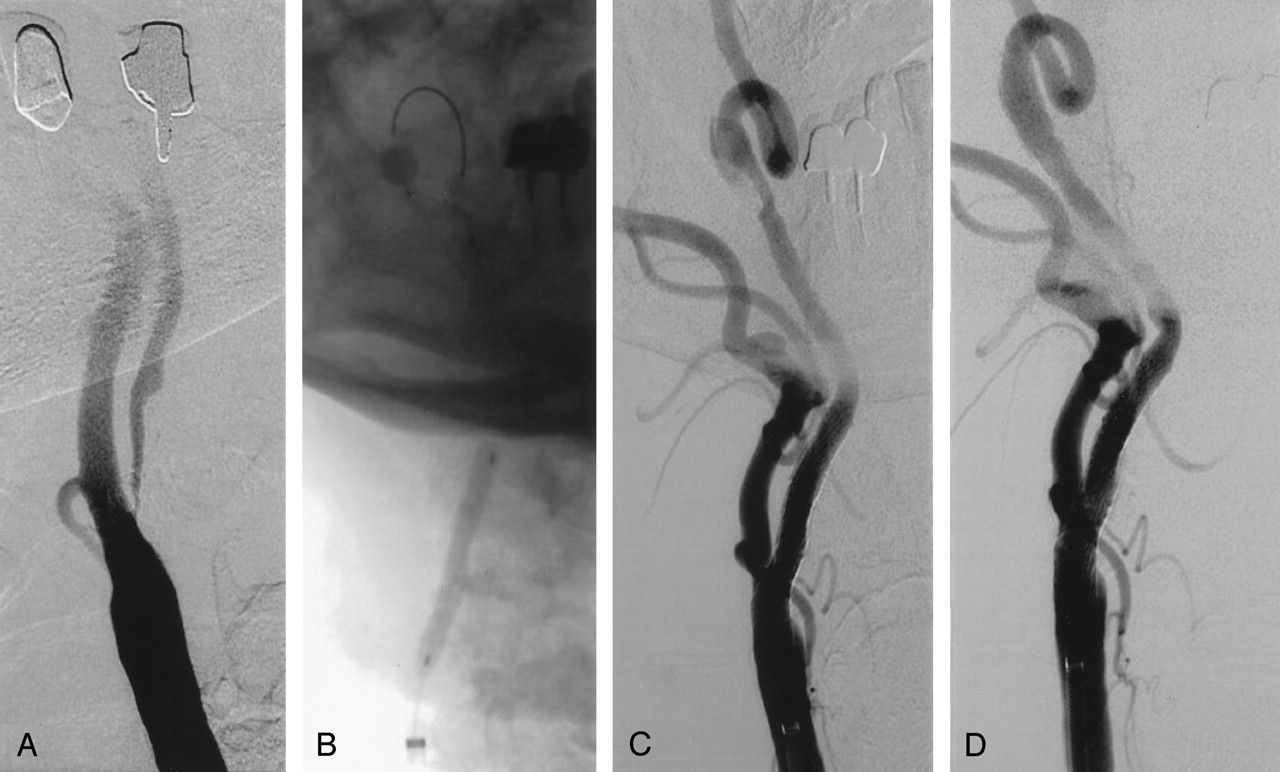

A and B, Illustration of the buddy catheter technique in a 70-year-old man.

A, Left, Left carotid angiogram shows near occlusion of the ICA. The 90° takeoff angulation made advancement of the GuardWire temporary occlusion catheter into the stenotic ICA impossible. Right, Angiogram shows the buddy catheter (5F, 125-cm JR4, arrow) positioned through a 6F guiding sheath, with its tip pointing into the angulated ICA lesion. The temporary occlusion catheter is advanced through the stenosis into the distal segment of the ICA.

B, Left, Angiogram shows that the inflated balloon of the temporary occlusion catheter is occluding the ICA. Right, Angiogram obtained after carotid artery stent placement. Two 10 × 30-mm Smart stents were deployed.